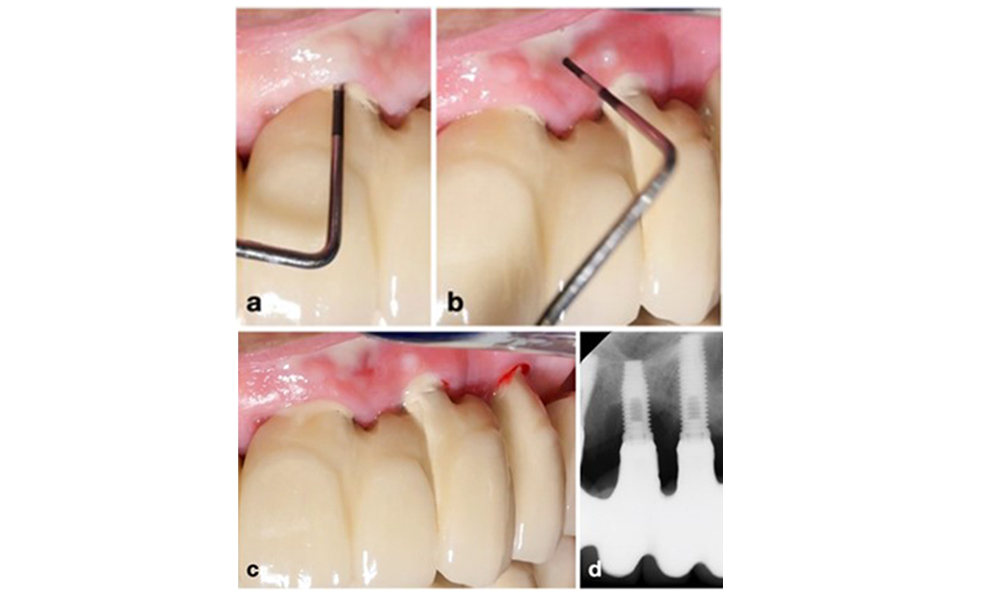

Периимплантитът се идентифицира чрез (1) признаци на възпаление, подобни на мукозит, (2) рентгенографски данни за загуба на кост след първоначалното заздравяване и (3) увеличаване на дълбочината на сондиране в сравнение с измерванията, направени малко след поставянето на протезната реконструкция (фигура 2) . При липса на предишни рентгенографии, рентгенографско костно ниво ≥ 3 mm и кървене при сондиране и дълбочина на сондиране ≥ 6 mm показват периимплантит.

Очакваната костна загуба след първоначалното заздравяване се дължи на маргиналното костно ремоделиране и варира в зависимост от фактори като имплантна система или типа имплант. Например загуба на 1–2 mm кост обикновено се счита за „нормална“ за импланти на нивото на костта с външна връзка (фигура 2d, имплант в позиция 23).